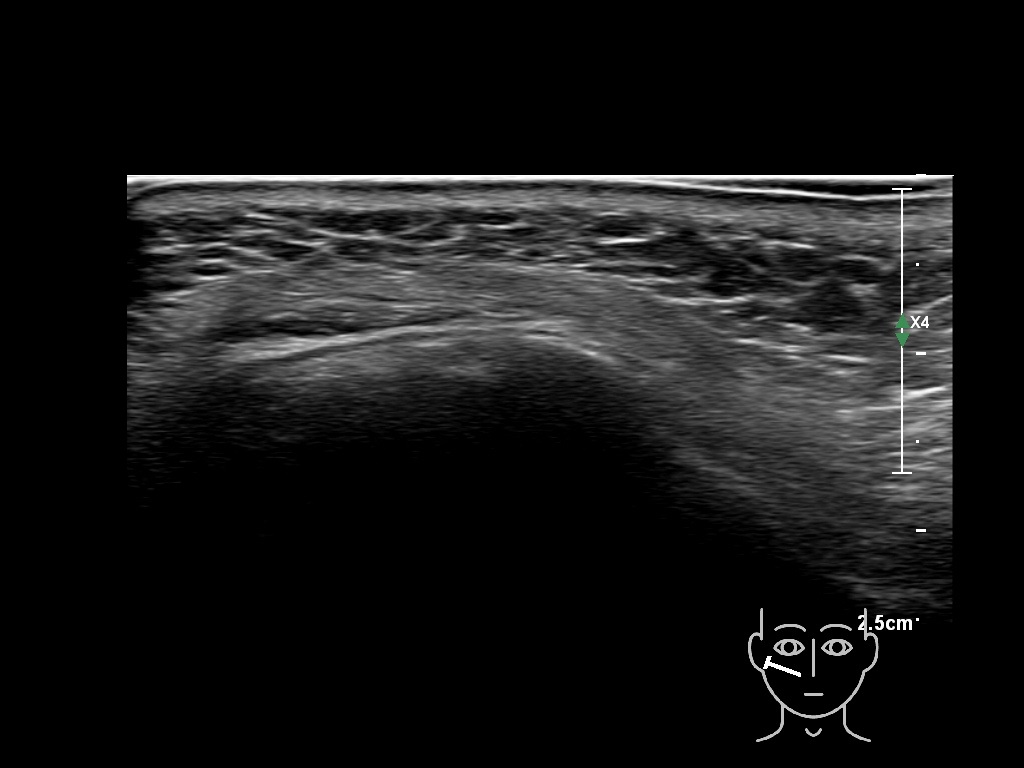

Draw in the second image below where the fillers are located. To check if your answer is correct, swipe the first image to the right.